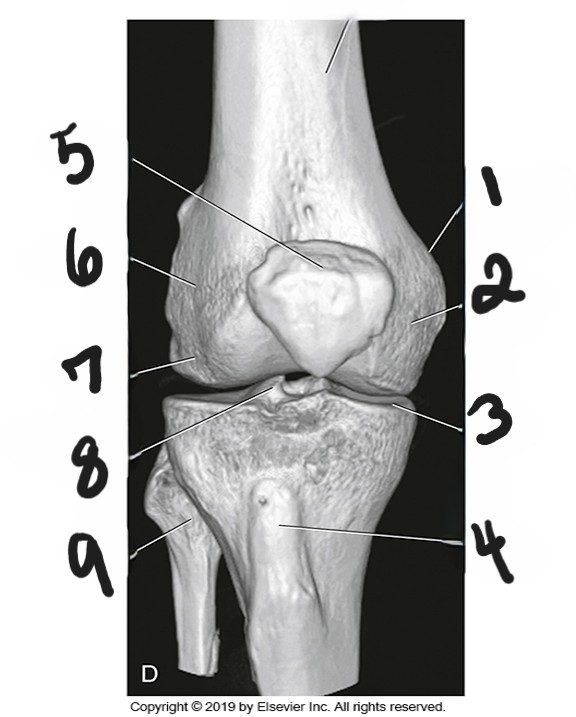

what is #1?

medial condyle

what is #2?

tibial plateau

what is #3?

tibial tuberosity

what is #4?

patella

what is #5?

lateral epicondyle

what is #6?

lateral condyle

what is #7?

intercondylar eminence

what is #8?

fibula

what is #9?